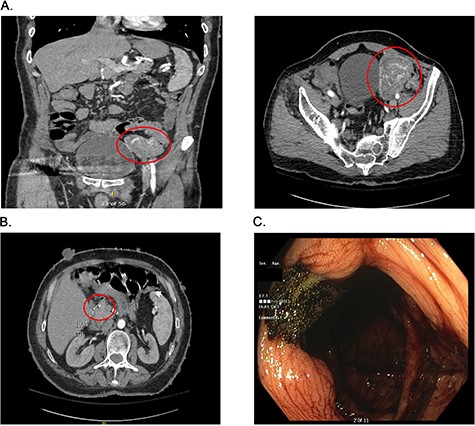

Presurgical diagnostics. (A) CT imaging of the large jejunal mass. (B) CT imaging of small duodenal mass. (C) Blood at the ileo-cecal valve.

On admission at the outside hospital, the patient’s hemoglobin was 6.6 g/dl, with normal platelets, partial thromboplastin time and prothrombin time. Diagnostic workup at the outside institution included a nuclear medicine gastrointestinal scan (mTc-labeled RBCs), which was negative for abnormal bleeding. On hospital Day 2, his hemoglobin failed to respond appropriately to transfusions and a computed tomography angiogram (CTA) was completed, which showed a 6.9 × 5.8 × 6.8 cm hyper-vascular mass in the left pelvis; abutting the left border of the bladder medially, iliac arteries and veins posteriorly, rectus sheath anteriorly and the small and large bowel (Fig. 1A). Vascular supply of the mass was identified to originate from branches of the superior mesenteric artery (SMA) and appeared to be contiguous with the adjacent jejunum. The mass was noted to also abut, but not involve, the sigmoid colon. The CT scan further noted a 9 mm enhancing tumor in the second portion of the duodenum anteriorly (Fig. 1B). After administration of five total units of packed red blood cells with limited improvement in hemoglobin, the patient was transferred to our institutions for further management.

The patient arrived hemodynamically stable and underwent esophagogastroduodenoscopy (EGD). The EGD was unremarkable with no visualization of the previously mentioned duodenal mass. Colonoscopy was performed, which was notable for bright red blood present throughout the entire colon as well as blood 5 cm proximal to the ileocecal valve (Fig. 1C). As the patient continued to have bloody output per rectum, with insufficient response to transfusion, interventional radiology was consulted and proceeded with mesenteric angiography with intervention (Fig. 2A). The hyper-vascular mass was found to be supplied by ileal branches of the SMA, which were successfully embolized (Fig. 2B and C). After conversations with the interventional radiology team and the patient, the decision was made to proceed with an exploratory laparotomy and resection of the identified mass.